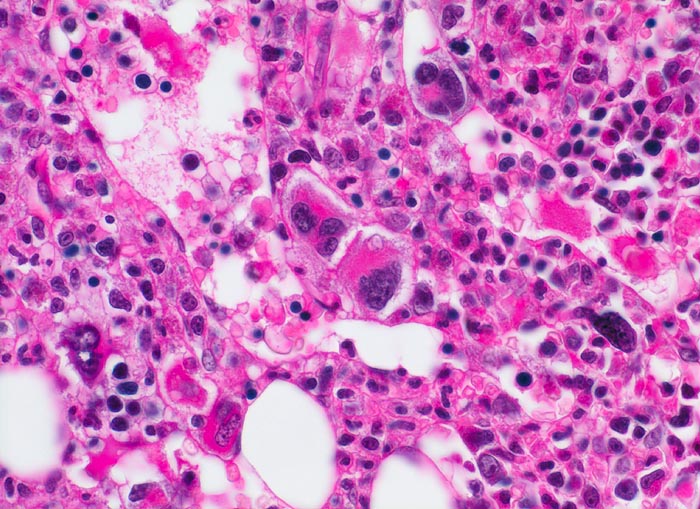

- Vermehrung von atypischen, in Gruppen liegenden Megakaryozyten mit abnorm lobulierten Kernen.

- Nacktkernige (zytoplasmaarme) und vergrösserte Megakaryozyten.

- Dilatierte Sinusoide mit intrasinusoidaler Blutbildung.

- Retikulinfaserfibrose des Marks vorhanden aber in der HE Färbung schwierig quantifizierbar.